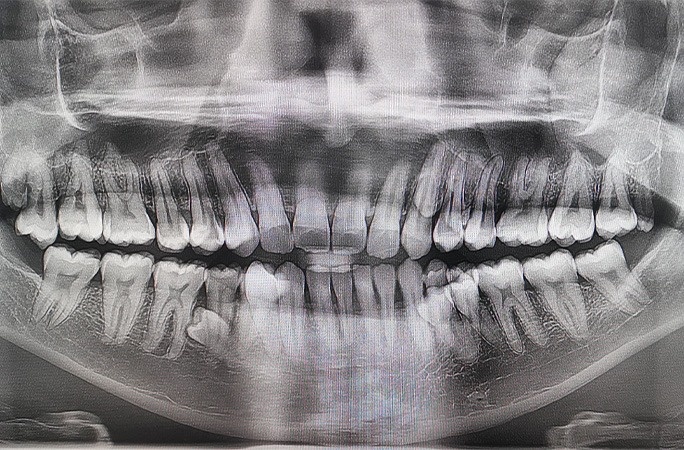

Ακτινογραφία από τα δόντια του Prathab Muniandy

Το στόμα του Muniandy περιείχε 42 δόντια, καθιστώντας την περίπτωσή του ένα ακραίο παράδειγμα υπεροδοντίας.

Οι περιπτώσεις υπεροδοντίας συνήθως περιλαμβάνουν μόνο ένα ή δύο επιπλέον δόντια, επομένως η ύπαρξη 10 επιπλέον δοντιών είναι εξαιρετικά σπάνια.